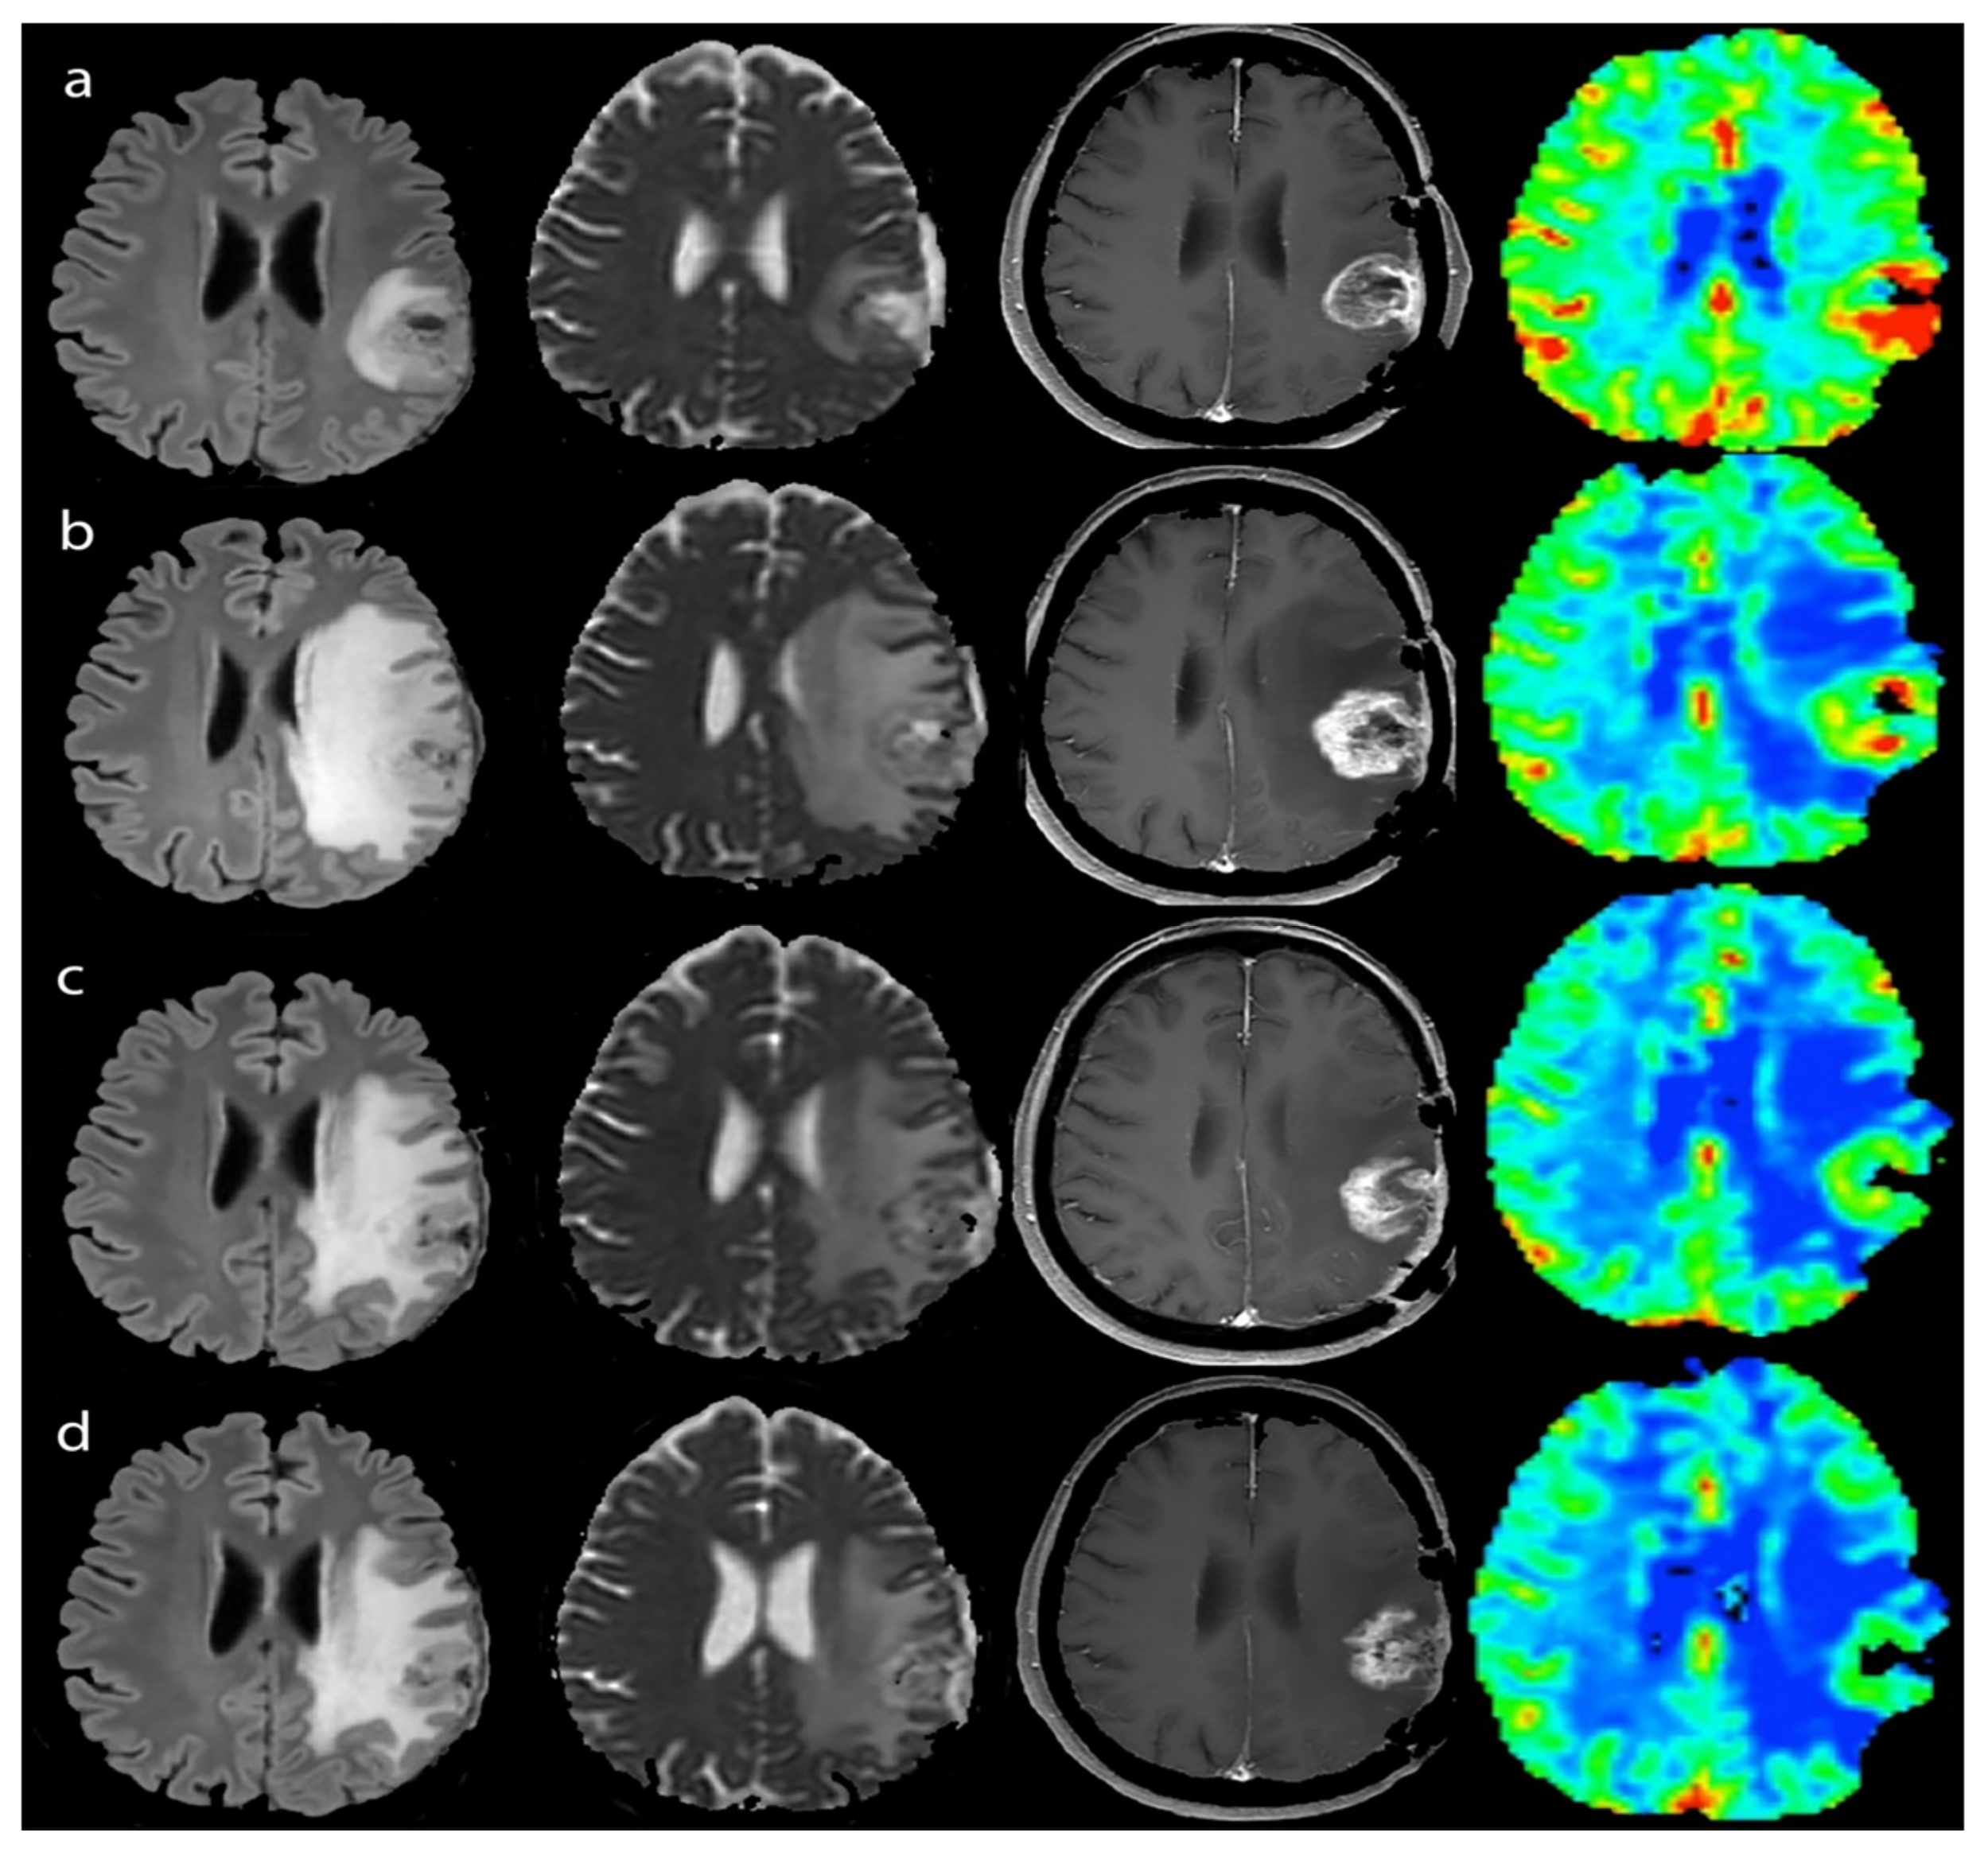

2.3.2. Perfusion

2.3.3. Diffusion

3.2.1. Response Assessment

3.2.2. Survival